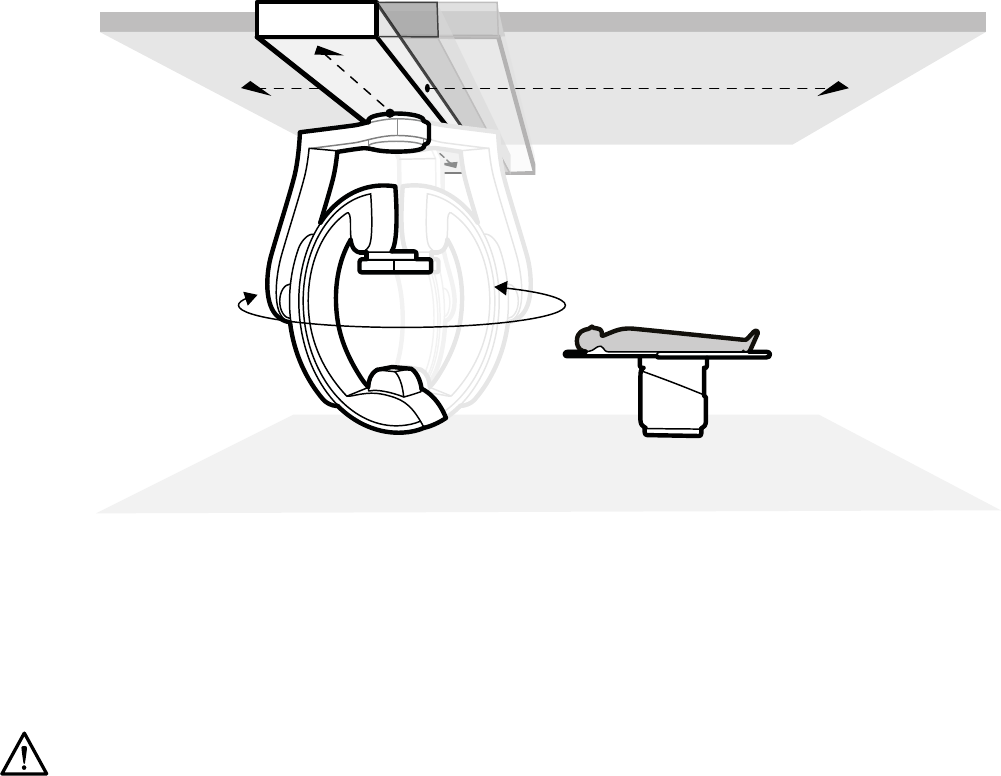

6.16 Skanowanie rotacyjne.......................................................................................................... 102

6.16.1 Wykonywanie skanu rotacyjnego w pozycji ustalonej......................................... 103

6.16.2 Wykonywanie skanu rotacyjnego w pozycji swobodnej.......................................103

6.16.3 Oprogramowanie XperCT.....................................................................................104

6.16.4 XperCT Dual......................................................................................................... 106

6.16.5 CardiacSwing........................................................................................................107